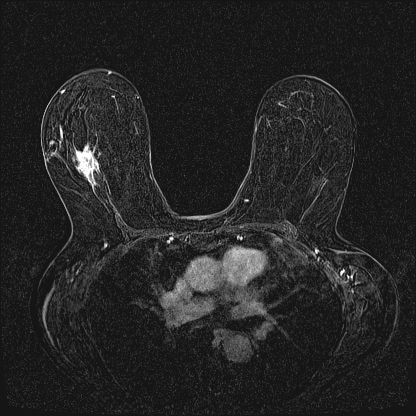

74-year-old presents with palpable lump in left breast, status post left lumpectomy for infiltrating ductal carcinoma with sequential radiation 16 years ago.

A 30-year-old who has been breastfeeding for three months presents for evaluation of a right breast lump that is nontender and has been present for two weeks.